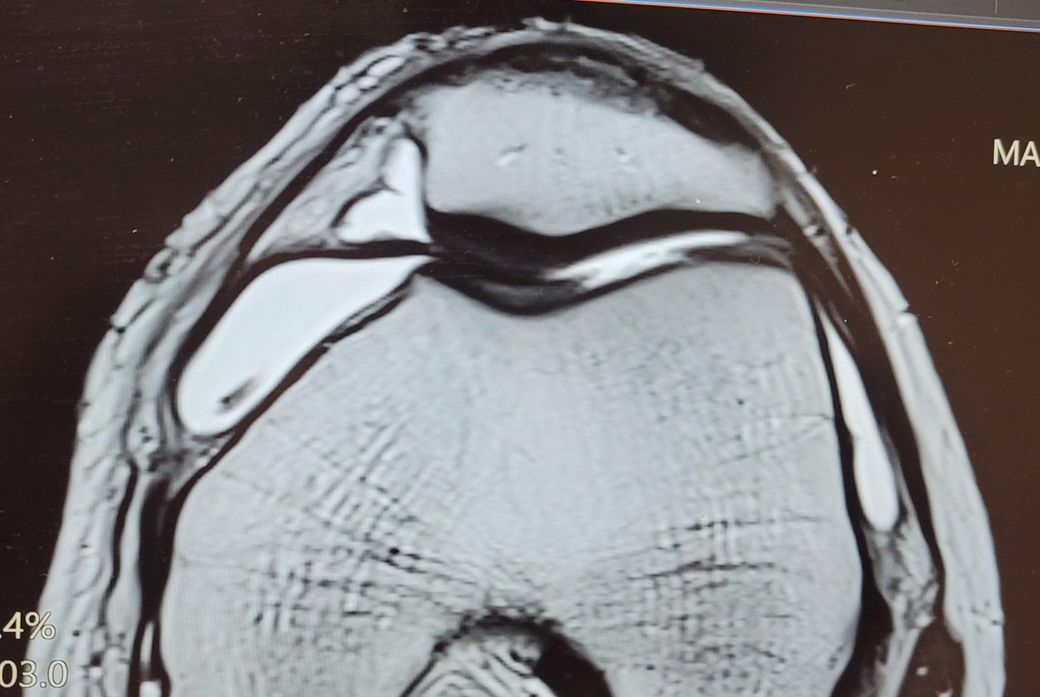

오른무릎 활차구 연골 결손 MRI 사진입니다

• 2번 째 사진

첨부하신 MRI 영상에서는 활차구의 연골 표면이 다소 불규칙하게 보이지만, 연골이 완전히 벗겨졌거나, 연골 아래 뼈가 드러나는 심한 손상은 명확하게 보이지 않습니다. 이러한 소견은 일반적으로 ICRS 분류상 2등급에 가까울 가능성이 있습니다. ICRS 2등급은 연골 표면에 결손이 있으나 깊이가 얕고, 연골하골까지 손상이 이르지는 않은 상태를 의미합니다.

다만 MRI만으로 정확한 등급을 단정하긴 어렵고, 실제 관절내시경과 같은 직접적인 확인을 통해 보다 정확한 진단이 가능합니다. 영상 해석은 촬영 각도, 기기 해상도, 해석자의 경험 등에 따라 달라질 수 있어, 세부적인 내용은 영상의학과나 정형외과 전문의와 직접 상담을 받으시는 것이 가장 안전합니다.